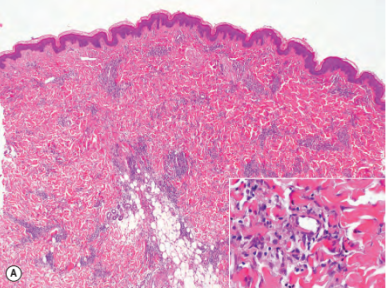

(圖3:在皮下細胞組織中排列著網(wǎng)狀的、增厚的膠原蛋白,沒有伴隨炎性滲出。如圖在血紅蛋白-噻唑啉染色下,放大20倍觀察。)

對患者進行自身免疫研究分析,并沒有發(fā)現(xiàn)到任何異常,而磁共振成像也排除了肌骨受傷的可能,以及皮膚活檢發(fā)現(xiàn)與皮膚僵硬綜合癥相似,復檢后發(fā)現(xiàn)皮膚深處有一層水平排列的增厚膠原蛋白,遵循網(wǎng)格狀排列,并且沒有炎性浸潤表現(xiàn)。在進行臨床與病理相關(guān)性分析后,診斷為DFC(先天性筋膜萎縮癥),醫(yī)師給予物理治療建議。

除了臨床表現(xiàn),顯微鏡下的發(fā)現(xiàn)也非常重要。在顯微鏡下,可以看到膠原組織的增生,特別是在肌筋膜和皮下脂肪組織中。需要強調(diào)的是,肌筋膜損傷并非此疾病診斷的必要條件。在最初的描述中,將“先天性筋膜萎縮癥”一詞提出,因為在所有這類患者中,肌筋膜都受到了影響。然而,隨后并未統(tǒng)一證實這種結(jié)構(gòu)的受損。DFC最特別與最顯著的顯微鏡檢查結(jié)果不僅在于多處膠原組織的增生,更多體現(xiàn)在其呈現(xiàn)出網(wǎng)狀的排列形態(tài)。其他典型發(fā)現(xiàn)包括缺乏炎性浸潤和粘液存在。